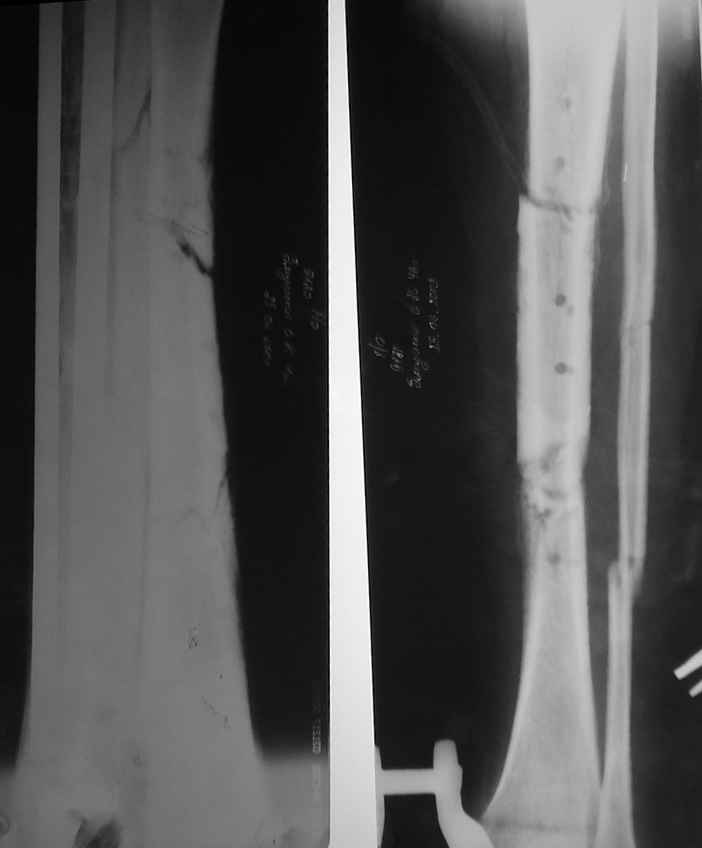

Пациент 42 лет около 3-х месяцев лечился на районе с открытым двойным переломом большеберцовой кости на границе верхней и средней трети и на границе нижней и средней трети,двойным переломом малоберцовой кости. Прооперирован на районе в день поступления- произведен остеосинтез перелома большеберцовой кости металической пластиной. В послеоперационном периоде некроз краёв раны по передней поверхности голени, нагноение, остеомиелит. Была попытка свести края раны путём нанесения послабляющих разрезов по боковым поверхностям голени.При поступлении в наш центр у пациента обширная рана передней поверхности голени с дефектом мягких тканей, в ране на большом протяжении обнажена нежизнеспособная тусклая большеберцовая кость, в том числе зона перелома. Отделяемое из раны гнойное с неприятным запахом. На операции после резекции осцилирующей пилой передней поверхности обнажённой части большеберцовой кости, в костно-мозговом канале большое количество гноя, задняя поверхность большеберцовой кости тусклая. Некрэктомия и остеосеквестрэктомия, из костно-мозговых каналов оставшихся верхнего и нижнего отрезков большеберцовой кости умеренное кровотечение. Произведена транспозиция мышечного лоскута передней большеберцовой мышцы на ветвях передней большеберцовой артерии в область ложа большеберцовой кости, мышцей закрыты верхний и нижний отрезки большеберцовой кости. На мышечное ложе уложены свободные расщеплённые мышечные лоскуты, взятые с правого бедра. Произведен стабилизирующий остеосинтез правой голени спицами,фиксированными и натянутыми в аппарате Иллизарова. В послеоперационном периоде лоскуты хорошо фиксированы, рана чистая, по дренажам скудное отделяемое геморрагического характера. Дренаж сегодня удалил. Планируется после полного востановления кожного покрова и консолидации перелома малоберцовой кости, транспозиция и фиксация последней на область дефекта большеберцовой кости. Одномоментно побоялись сделать такую оперцию из-за риска развития остеомиелита малоберцовой кости, так как оперировали на фоне выраженных гнойных осложнений.Фото прилагаю.С уважением, Цветков Евгений.

В настоящее время целостность мягких тканей голени полностью восстановлена, кожные лоскуты на мышце розовые фиксированные, раны закрыты на 100%, больной активен, ходит на костылях с дозированной нагрузкой на ногу в аппарате. Планируем выписать его на месяц по месту жительства. И если не получится с Минском, сделаем ему как и планнировали что-то вроде операции Гана-Кодивилла-Геттингтона. Пациент заранее настроен на длительное лечение в аппарате Иллизарова, уже хорошо адаптирован,оптимистичен и пока очень доволен результатами, отмечает значительное улучшение самочувствия. В приложении высылаю фотографии рентгенограм до и после операции.